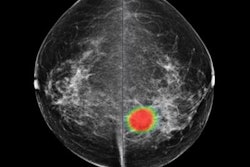

Breast cancer can be diagnosed, staged, and tracked using a variety of imaging modalities, including FDG-PET/CT, which can be a particularly powerful tool due to its ability to image both anatomy and metabolic function.

But how best to use FDG-PET/CT for breast cancer must be clearly defined, according to a presentation delivered on 28 May at a webinar hosted by the European Society for Hybrid, Molecular, and Translational Imaging (ESHIMT) and featuring Dr. José Vercher-Conejero of Bellvitge University Hospital in Barcelona, Spain. Find out what he had to say about using the modality for breast cancer applications, particularly staging and treatment assessment, in our recent report.